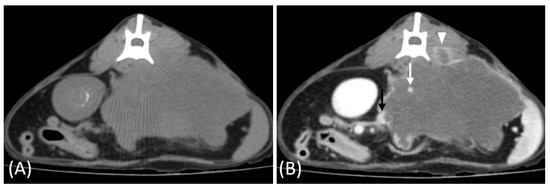

Figure 1.

(A) Pre-contrast, (B) corticomedullary phase, (C) nephrographic phase, and (D,E) late nephrographic/early excretory phase contrast-enhanced computed tomography (CT) images of a cat with a unilateral left renal cell carcinoma. The mass is heterogeneous, with tumor vessel enhancement (white arrow) noted in the corticomedullary phase. Progressive enhancement is observed, along with internal necrosis (black arrow). The renal vein is enlarged with tumor invasion (asterisk), but no invasion into the caudal vena cava (CVC) is seen. The tumor encases the renal artery, though definitive arterial invasion is not apparent.